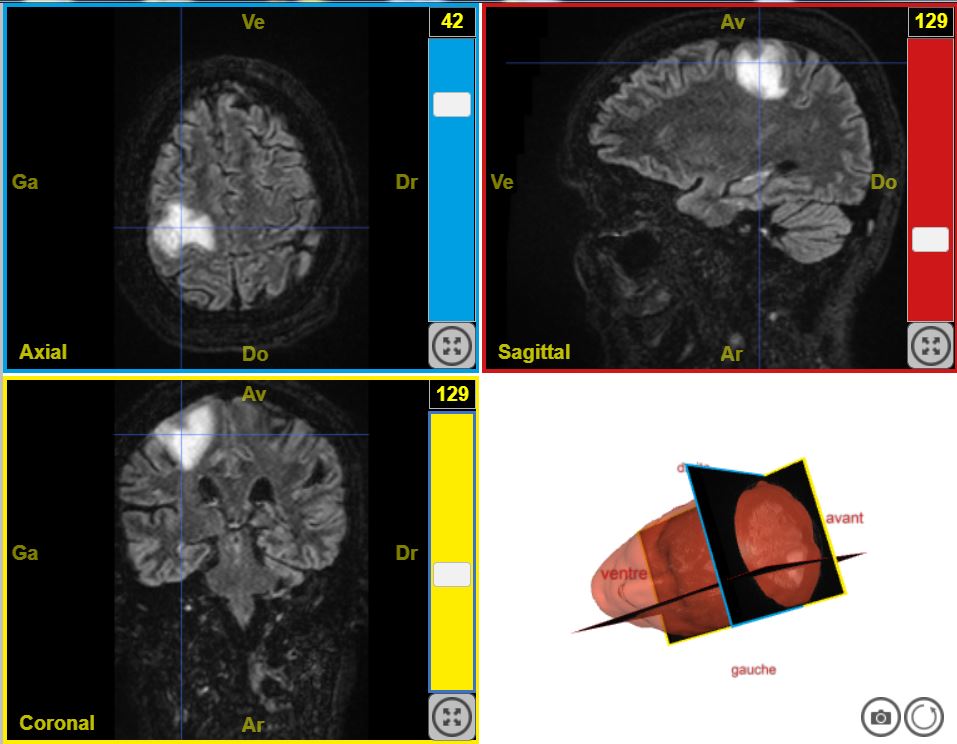

Deficit moteur T2 Flair